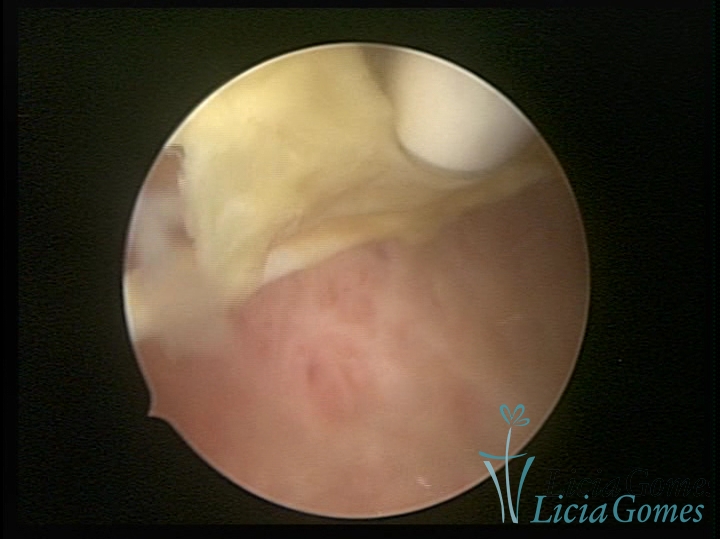

Trophic cervical canal with Mirena string®